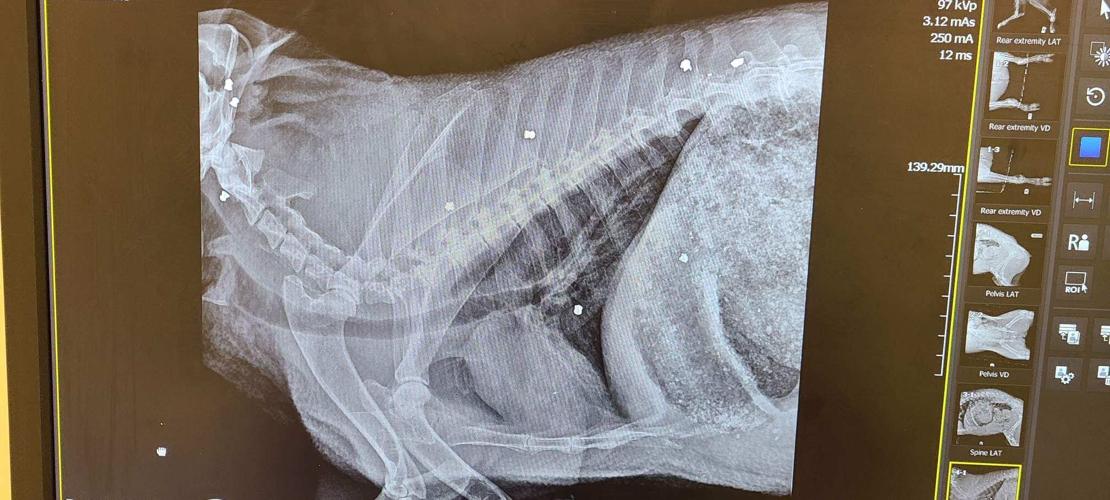

Another X-ray view of the wounds to the javelina.